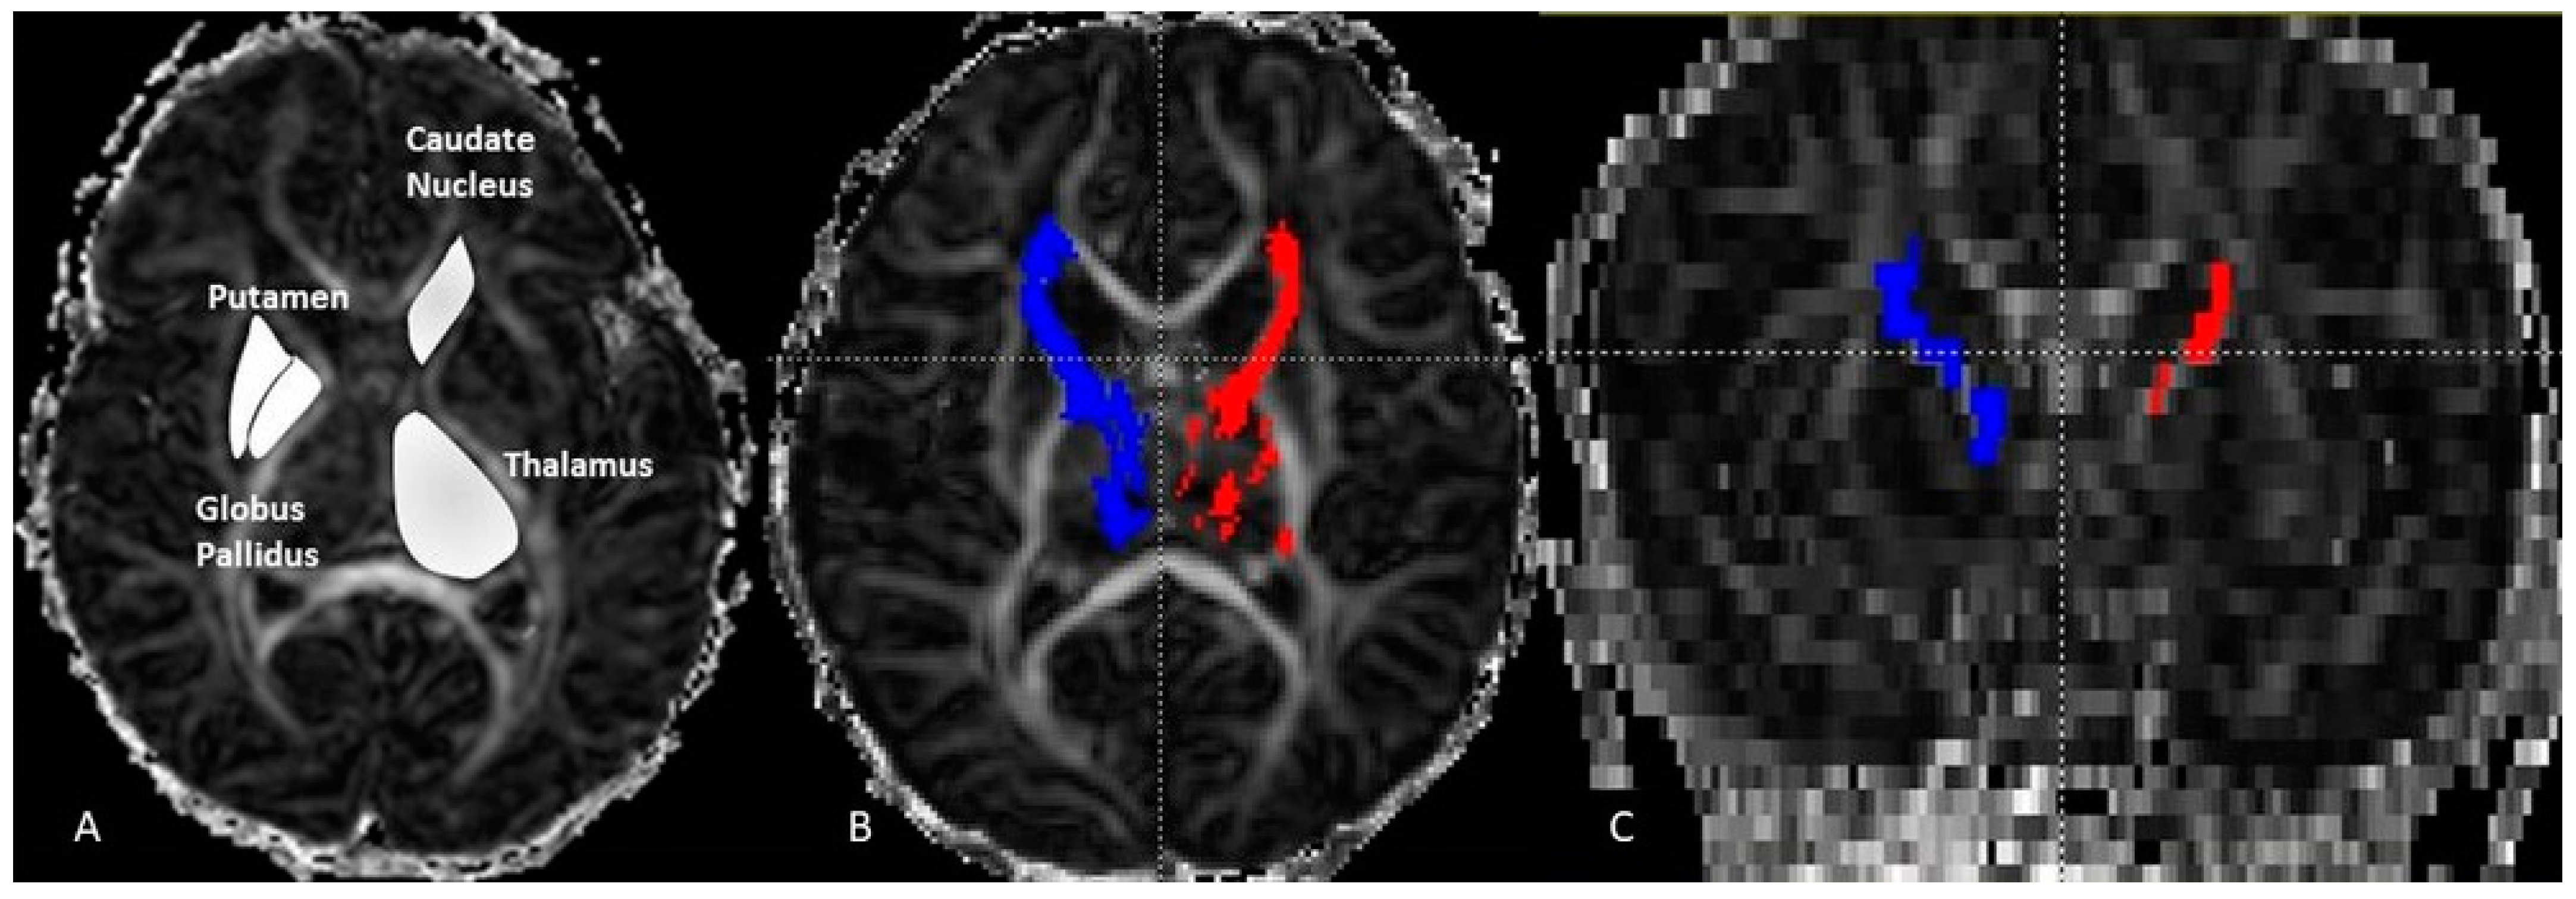

The thalamo-cortical fiber (THC) tracking was carried out with DTI Studio software (Department of Radiology, Johns Hopkins University, Baltimore, MD, USA) using the deterministic FACT algorithm (fiber assignment continuous tracking) and the following two rejection criteria: fractional anisotropy (FA) < 0.15 or angulation > 70°. The seed regions were manually drawn on each axial slice of the TH on FA maps (4 to 5 slices). It has been applied with the inclusive “OR” operator. The target regions were selected FA maps at the coronal plane at the level of the genu. This was performed with an exclusive operator “AND”. It was reproduced bilaterally to determine left and right THC pathways. The axial diffusion (AD), the radial diffusion (RD), the apparent diffusion coefficient (ADC) and the FA were measured and averaged separately over the entire left and the entire right THC. For each group (girls, boys and combined) we measured the DTI variables bilaterally on the selected four structures: TH, PT, GB, and CN (Figure 1).

Figure 1.

Axial fractional anisotropy (FA) image (A) displaying the ROI manual drawing on the thalamus, caudate-nucleus, putamen and globus pallidus. On the (B) image the result of fiber tracking of the left (red) and right (blue) thalamo-cortical pathways. The same pathways are displayed in the coronal plane (C). These were performed on a neonate girl (GA = 43 weeks + 3 days).